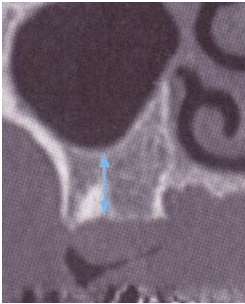

鼻竇黏膜本身本來就容易破,越薄越容易破。 我們有沒有可能在手術前就預估手術患者的黏膜,究竟是厚還是薄嗎?

Almetti設計了一個study去研究,是否gingival thickness和鼻竇黏膜的厚度有相關? 結果發現:鼻竇黏膜的一般厚度為0.97mm, 當遇到較厚的牙齦組織時,鼻竇黏膜增加到1.26mm;較薄的竇黏膜則只有0.61mm 。 所以這篇研究的結論認為牙齦厚度和鼻黏膜厚度是有關的(註5); 所以當我們遇到thin gingival biotype時, 就要假定鼻竇黏膜可能比較薄,而更加小心。